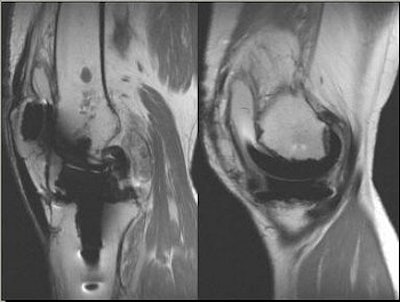

![]() |

Above, 68-year-old female who underwent TKA in 2001. Extensive particle disease, suspected split through the polyethylene at the posteromedial margin of the tibial tray and diffuse resorption of bone around the femoral component, indicative of loosening. Middle and below, TKA with large burden of particle disease (red arrow), which caused loosening of the patellar backing (white arrows). All images courtesy of Dr. Douglas Beall.

While the use of MR for particle disease is controversial, Beall pointed out that the modality, when used correctly, can clear up any confusion on other imaging tests, such as bone scan and arthrography, as well as offer a clearer picture of highly suspicious areas after total knee arthroplasty.